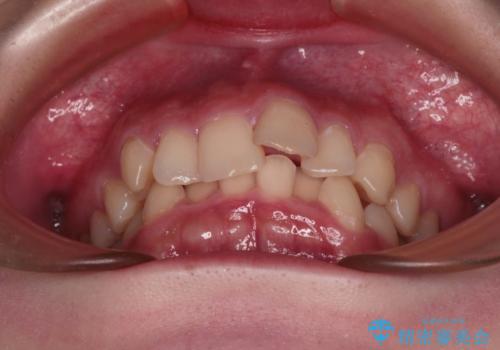

- デコボコになっている前歯を気にして来院された患者様です。

口元の突出感は気になっていないものの、デコボコを解消すると口元が前方に突出する可能性があるため、上下左右の第一小臼歯4本を抜歯して、ワイヤー装置にて矯正治療を行うこととしました。

下の前歯が隠れてしまうほど深く咬みこんでいたため、上顎前歯が前方に突出しているような印象がありましたが、咬み合わせが改善され、整った口元に仕上げることができました。